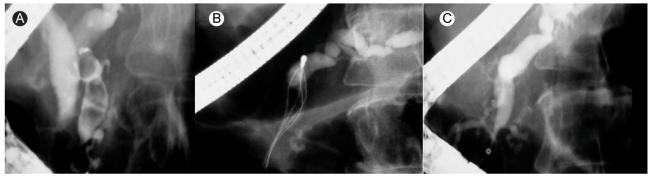

Update on endoscopic treatment of chronic pancreatitis.

Endoscopic therapy has been increasingly recognized as the effective therapy in selected patients with chronic pancreatitis. Utility of endotherapy in various conditions occurring in chronic pancreatitis is discussed. Its efficacy, limitations, and alternatives are addressed. For the best management of these complex entities, a multidisciplinary approach involving expertise in all pancreatic specialties is essential to achieve the goal.

内镜治疗已越来越被认为是慢性胰腺炎特定患者的有效治疗方法。本文讨论了内镜治疗在慢性胰腺炎各种情况下的应用。阐述了其疗效、局限性及替代方案。对于这些复杂疾病的最佳管理,多学科方法(包括所有胰腺专业的专业知识)对于实现目标至关重要。